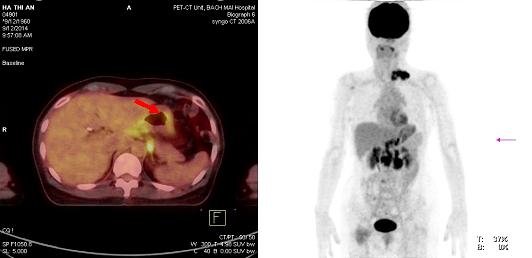

Hình 3: Hình ảnh dày thành dạ dày, tăng hấp thu 18F-FDG, max SUV: 3,74 (mũi tên đỏ).

Hình 4: Hình ảnh nhiều tổn thương di căn hạch ổ bụng tăng hấp thu 18F-FDG, kích thước từ 2,1- 8,8cm, max SUV: 8,52 (mũi tên vàng)

Hình 5: Hình ảnh tăng hấp thu 18F-FDG hạch thượng đòn trái, nhiều hạch kích thước 1,5-2,5 cm tạo thành chùm kích thước 6,2x3,2x3,6cm, max SUV: 8,7(mũi tên đỏ)